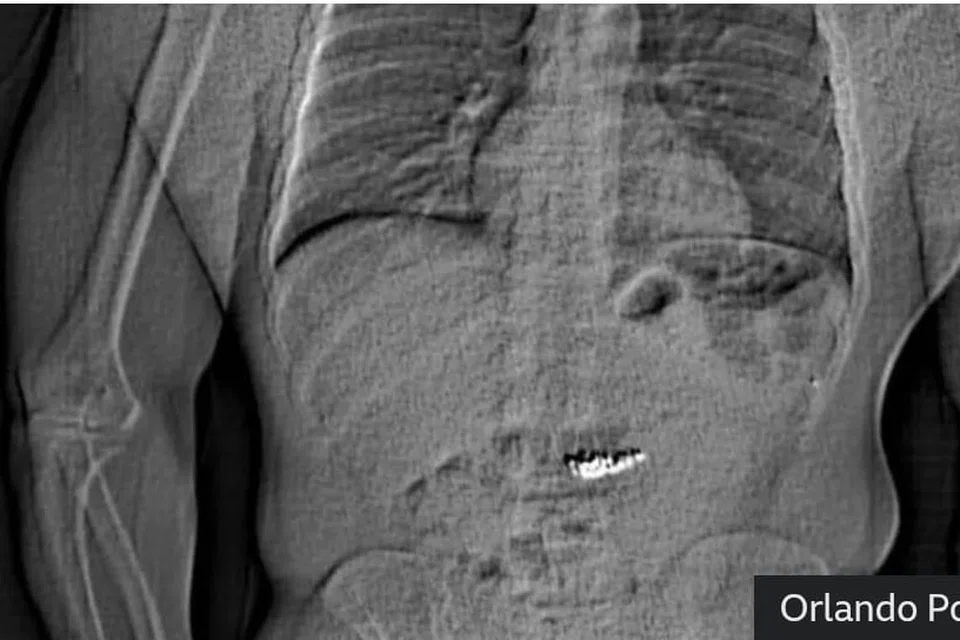

Hasil imbasan X-ray menunjukkan terdapat objek asing dalam saluran pencernaan Gilder, yang dipercayai barang kemas dari butik mewah tersebut.